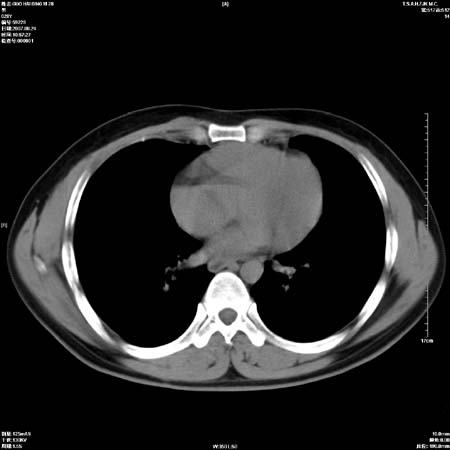

男性,28岁,体检发现左肺病变,患者只有背部隐痛感,哀哉,真不忍心下诊断啊。

左肺门区软组织肿块,左肺上叶支气管开口消失,纵隔内见肿大淋巴结,考虑左中心型肺部,可以做纤支镜取病理确认.

左肺肺门区肿块影,分叶明显,左肺上叶支气管开口受压,纵隔内见肿大淋巴结,考虑左中心型肺癌。

支持左上叶中央型肺癌伴纵隔淋巴结转移.

左上叶中央型肺癌伴纵隔淋巴结转移

直接下肺癌诊断还太早,病灶较大,估计5cm以上,但阻塞性改变及对临近纵隔及支气管侵犯不明显,密度较均匀,弓旁见一单个淋巴结,需要排除炎症性肿块及腺瘤,平滑肌瘤等。

肺癌并纵隔淋巴结转移。

左肺中心型肺癌并纵隔淋巴结转移!考虑为小细胞肺癌,没有手术机会了,只能进行放化了,疗效不错,但极易复发。没办法,现在肿瘤年轻化越来越明显了。